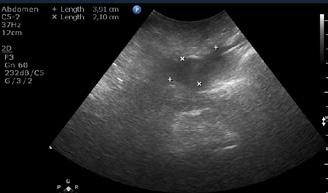

A opera sau a nu opera? Raspunsul ecografistului

Dr. Dan Adrian Stănescu 24